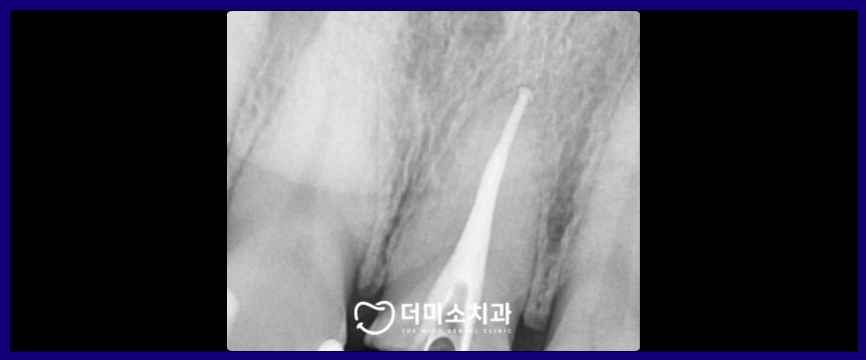

광명동치과 더미소치과에서는

내부의 치아가 손상되지 않도록

조심스럽게 기존 보철물을 제거한 뒤

기존의 충전제를 제거하고

신경관을 소독 및 성형을 진행하며

근관 내부를 깨끗하게 하였으며,

새로운 충전재를

뿌리 끝까지 빈틈없이 채워 넣으며

재신경치료를 마무리하였습니다.

신경치료 마무리 후

신경관 개방을 위해

구멍을 낸 치아머리 부분을

코아 레진으로 단단히 메워드리며

세균이 신경관으로 들어가는 것을

막아주었습니다.